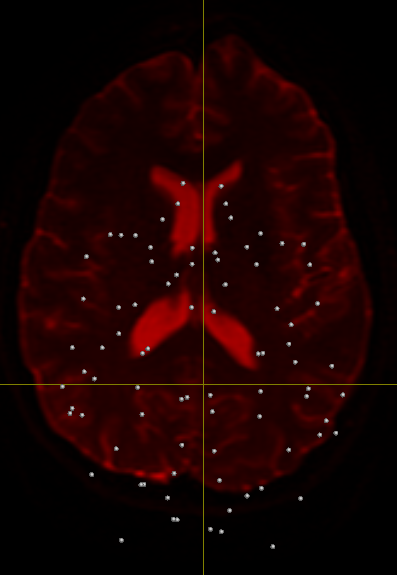

but I cant see the output images. However, I can overlay the nodes obtained

from the generic FreeSurfer's segmentation on the b_zero image of my data

set and I find that they a few nodes are ploted out of the brain area.

How could I fix this issue?

Name: aparc+nodos+b0.png